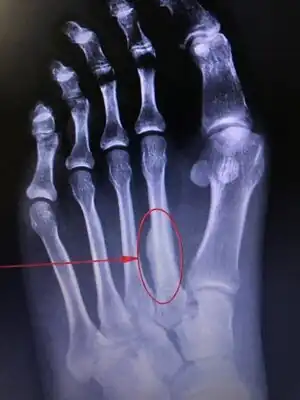

| Stress fracture of the second metatarsal bone | |

March fracture, is the fracture of the distal third of one of the metatarsals occurring because of recurrent stress. It is more common in soldiers, but also occurs in hikers, organists, and people whose duties entail much standing (such as hospital doctors). March fractures most commonly occur in the second and third metatarsal bones of the foot.[1][2][3] It is a common cause of foot pain, especially when people suddenly increase their activities.[4]

X-ray is seldom helpful, but a CT scan and an MRI study may help in diagnosis.[5] Bone scans are positive early on. Dual energy X-ray absorptiometry is also helpful to rule out comorbid osteoporosis.[6]